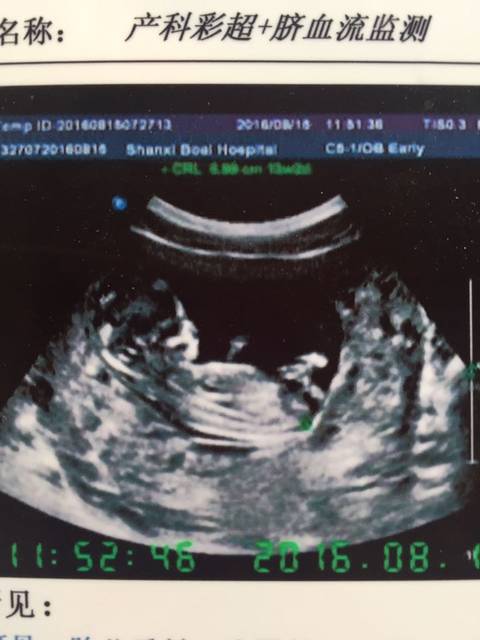

b超图看男女_13周b超图,大家看看是男是女_宝宝树

480x640 - 34KB - JPEG

13周,nt、b超图,有会看男女的大神吗_帮我看下跪谢啦_宝宝树

609x640 - 33KB - JPEG